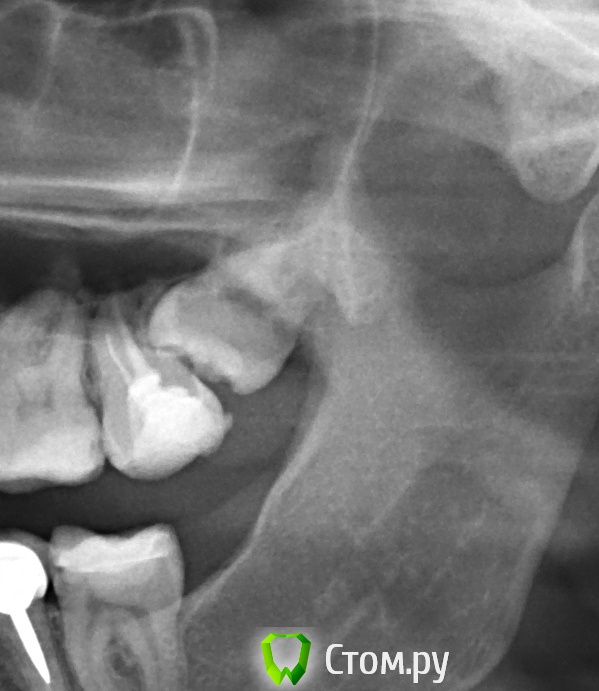

Чертков Александр Опубликовано 28 ноября, 2013 Поделиться Опубликовано 28 ноября, 2013 Из темы "И так бывает..."Сегодня вынул.http://s2.ipicture.ru/uploads/20131128/gh2jaMJr.jpg 4 Ссылка на комментарий

Чертков Александр Опубликовано 28 ноября, 2013 Поделиться Опубликовано 28 ноября, 2013 да я не против,просто как предложение Спасибо. К тому же это 3.8...а это ведь Галерея 8к? 1 Ссылка на комментарий

samsonov Опубликовано 10 декабря, 2013 Поделиться Опубликовано 10 декабря, 2013 Пазуха аж сквозняком зашипела))) 4 Ссылка на комментарий